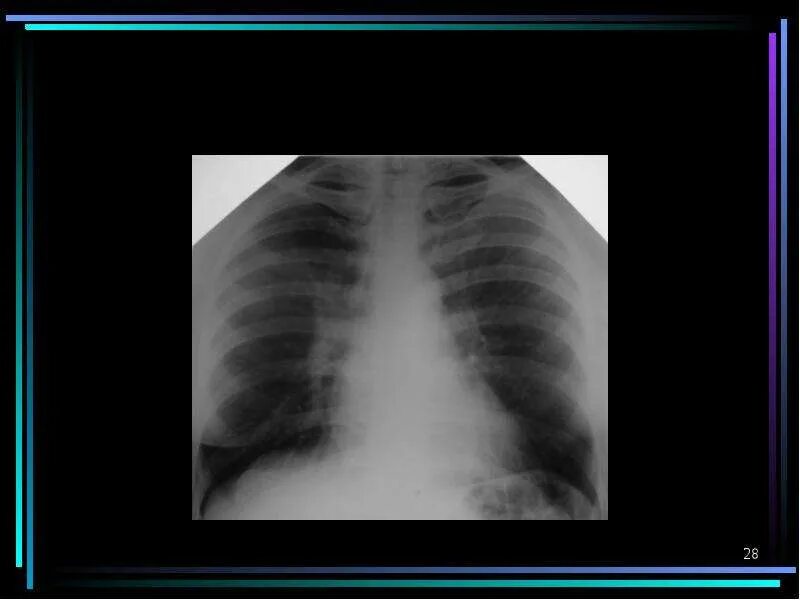

Легочные поля без очаговых и инфильтративных